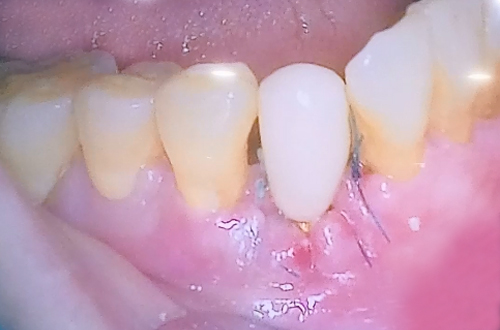

임시치아를 완성하여 마무리한 상태로 임플라트가 뼈와 단단하게 붙는 기간

4개월 정도 충분히 기다렸다가 옆에 있는 치아 색상과 똑같이 제작해서

예쁜 보철을 제작해 드릴 예정입니다.

추후에 임플란트 수술이 진행되고 보철도 완성이 되면

다음 진료일지로 다시 찾아뵙도록 하겠습니다^^!